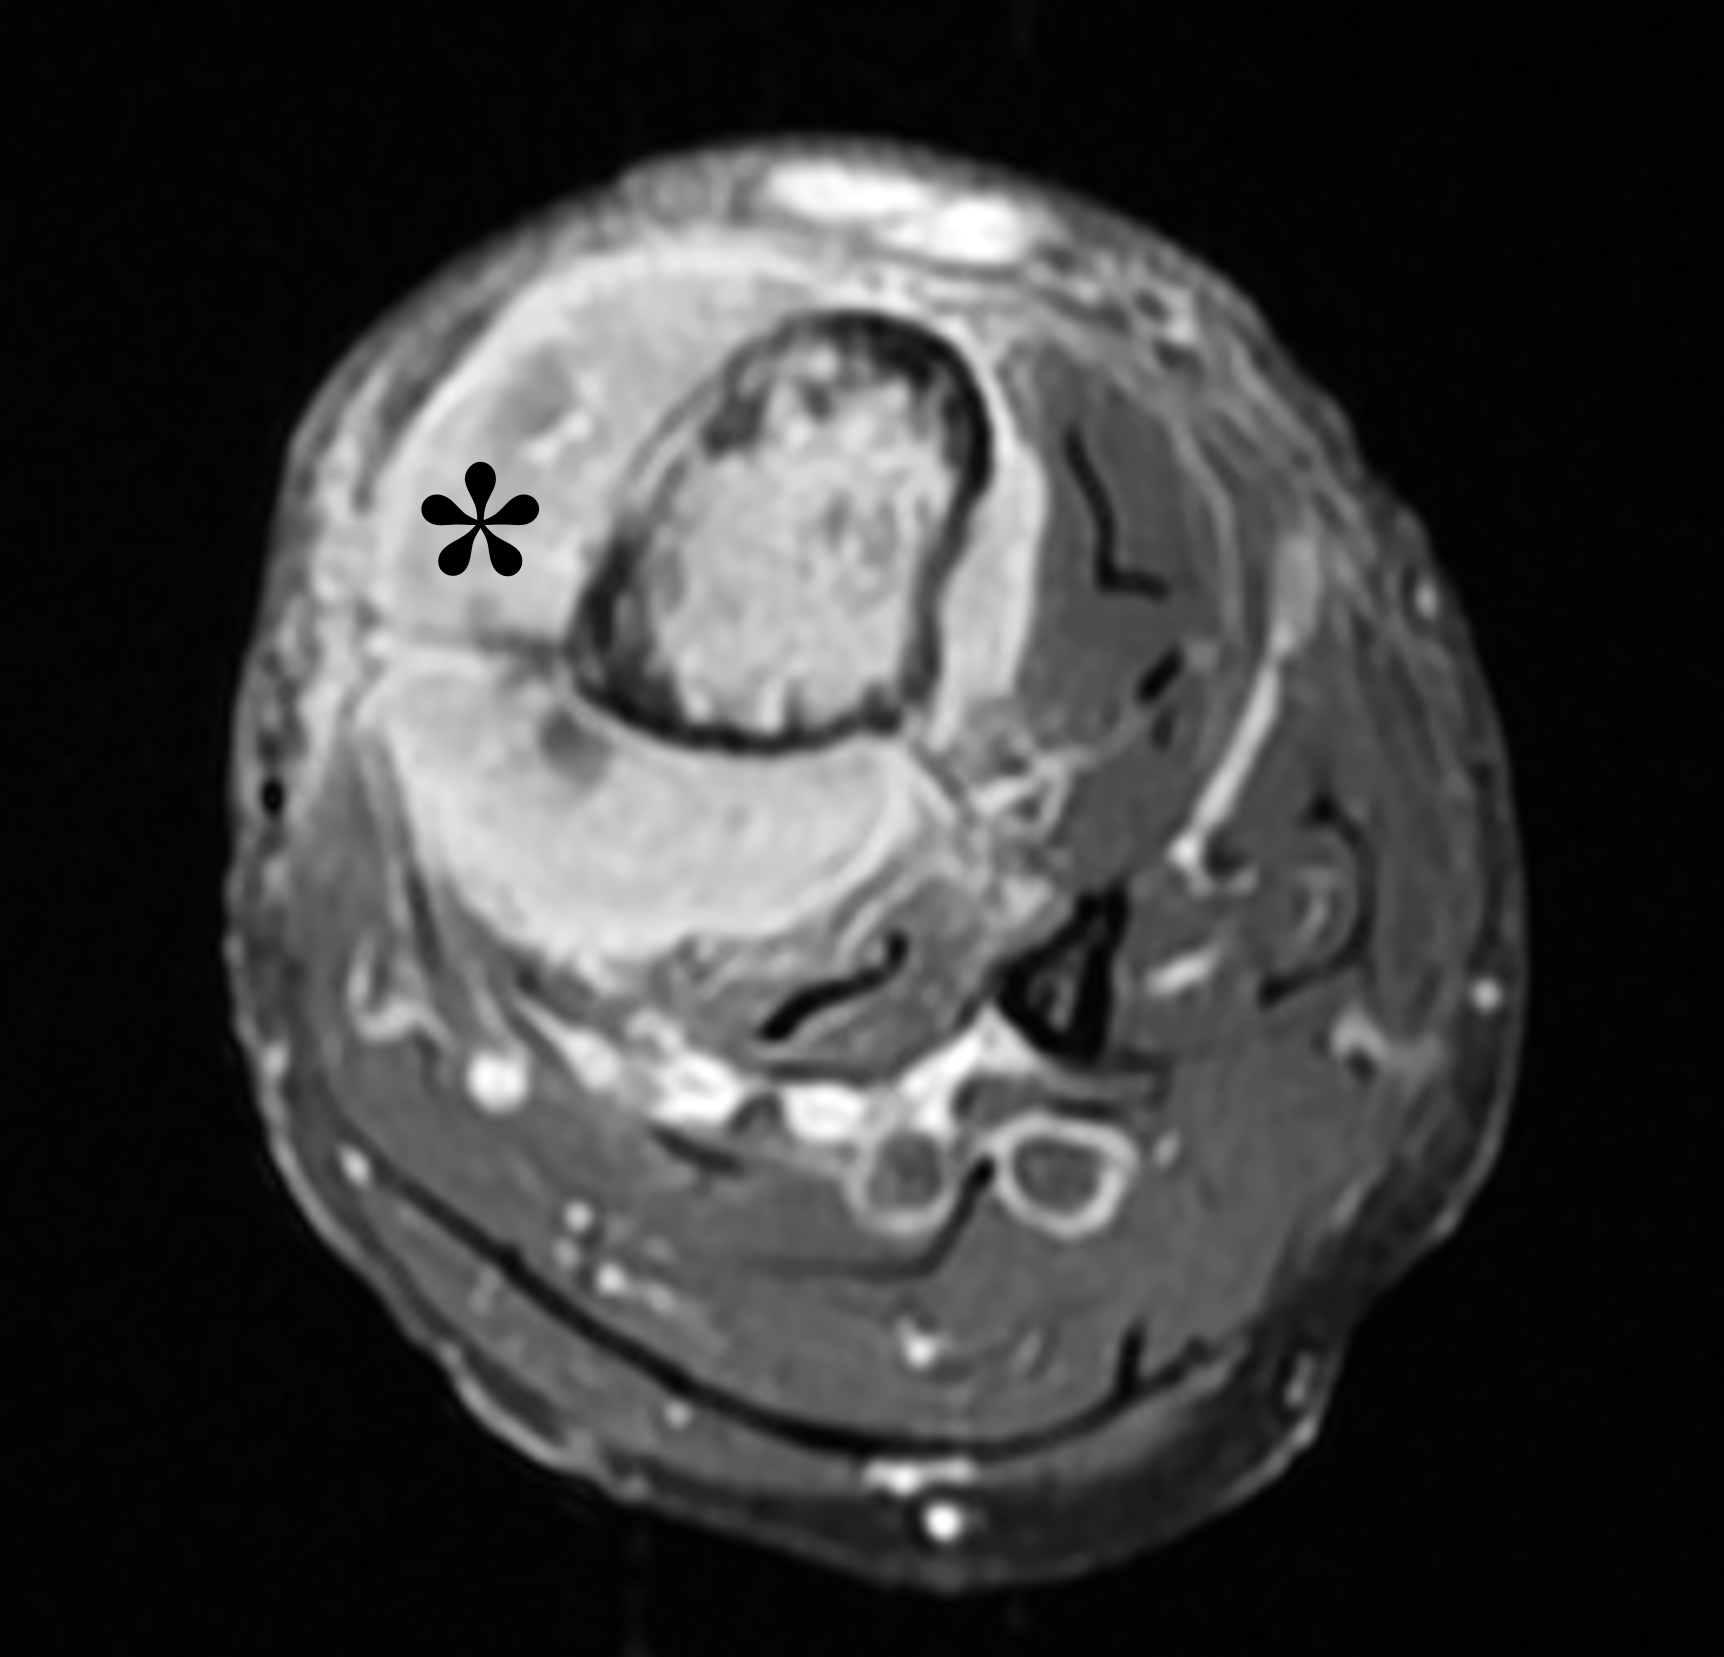

Figure 2: (2A) Sagittal T1-weighted image shows severe thickening of the distal femoral cortex (yellow arrow) and thickening and coarsening of the trabeculae in the femoral condyles (red arrow). Note the high signal intensity fatty marrow in both regions. (2B) Axial fat-suppressed, fluid sensitive sequence through the distal femoral shaft shows severe thickening of the bone cortex, with small round and tubular high-signal intensity foci within the cortex (arrow), likely representing cysts and dilated vascular spaces. (2C) Axial fat-suppressed, fluid sensitive sequence through the femoral epicondyles shows heterogeneous marrow (asterisks), with areas of suppressed marrow fat, mildly increased marrow signal intensity, and small cyst-like lesions. (2D) AP radiograph shows typical findings of mixed phase Paget disease in the distal femur including cortical thickening, course trabeculae, and bone enlargement. Secondary medial compartment predominant osteoarthritis has developed, likely contributing to symptoms.

Figure 4: Mixed phase Paget disease of the proximal humerus in a patient with polyostotic disease, MRI pattern 2. (4A) Coronal fat-suppressed, fluid-sensitive image shows heterogeneous marrow (asterisk) with areas of suppressed fat, mildly increased signal, and cystic/tubular high signal intensity areas. (4B) Coronal T1-weighted image shows preserved fat signal (asterisk) within the marrow, as well as thick cortex and trabeculae. (4C) AP radiograph shows typical findings of mixed-phase Paget disease, beginning at the proximal end of the bone and extending distally. Note the sharp demarcation (dotted lines) separating abnormal from normal bone, forming a “flame-shaped” interface. (4D) Bone scintigraphy demonstrates polyostotic disease with intense tracer uptake in the left hemipelvis, sacrum, and a thoracic vertebra in addition to the right proximal humerus.